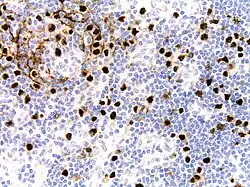

| Micrograph of HHV8-associated Castleman's Disease showing LANA-1 positive lymphoblasts in a regressed germinal center and mantle zone. LANA-1 stain. | |

Unlike the other subtypes of Castleman disease, UCD and iMCD, which can present with a spectrum of features on microscopic analysis (histology) of tissue biopsied from an enlarged lymph node, only a plasmablastic pattern of histologic features has been described in HHV-8-associated MCD. Plasmablastic features are similar to the plasmacytic features seen in iMCD and UCD, with both demonstrating increased plasma cells in interfollicular spaces. Plasmablastic features are differentiated from plasmacytic features by increased numbers of plasmablasts in follicular mantle zones.[10]

Staining with latency-associated nuclear antigen (LANA-1), a marker for HHV-8 infection, is typically positive.[11]